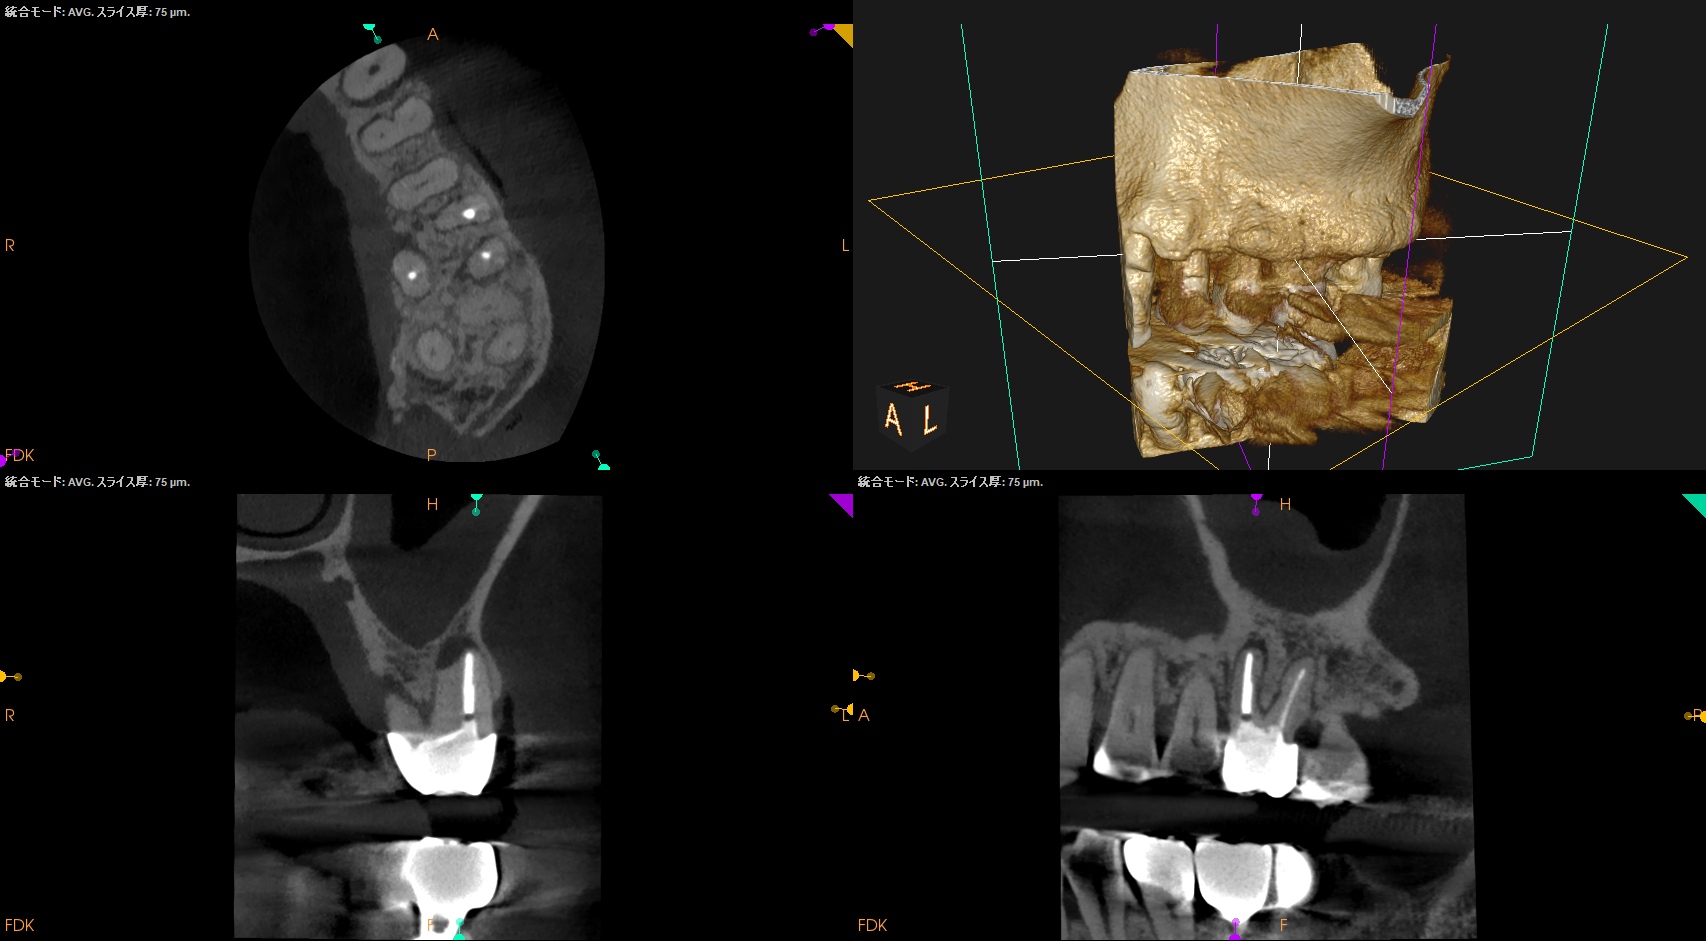

PA, CBCTを撮影した。

逆根管充填材が頬側に寄っているような絵である。

が、だ。

これはこのような切断部位で観察していることになる。

いわゆる、

歯軸と並行でないのである。

歯軸と並行になるようにCBCTのバーを動かした。

すると…

このような絵になる。